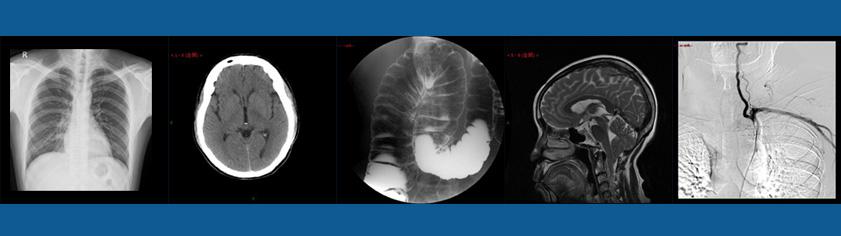

学科简短介绍 上海交通大学医学院附属仁济医院放射科是上海交通大学医学院重点学科,同时也是上海市教委重点学科。在上海市乃至全国享有较高的学术地位,特别在消化道、风湿病、肝胆疾病、淋巴系统、神经影像、磁共振功能分析、分子影像等传统和新兴的优势学科领域。 本学科具备绝佳的软硬件平台,硬件如3.0T多源磁共振、双能量能谱CT、专用介入磁共振、脑功能刺激仪,影像实验室。软件如功能影像分析系统、分子影像分析软件。